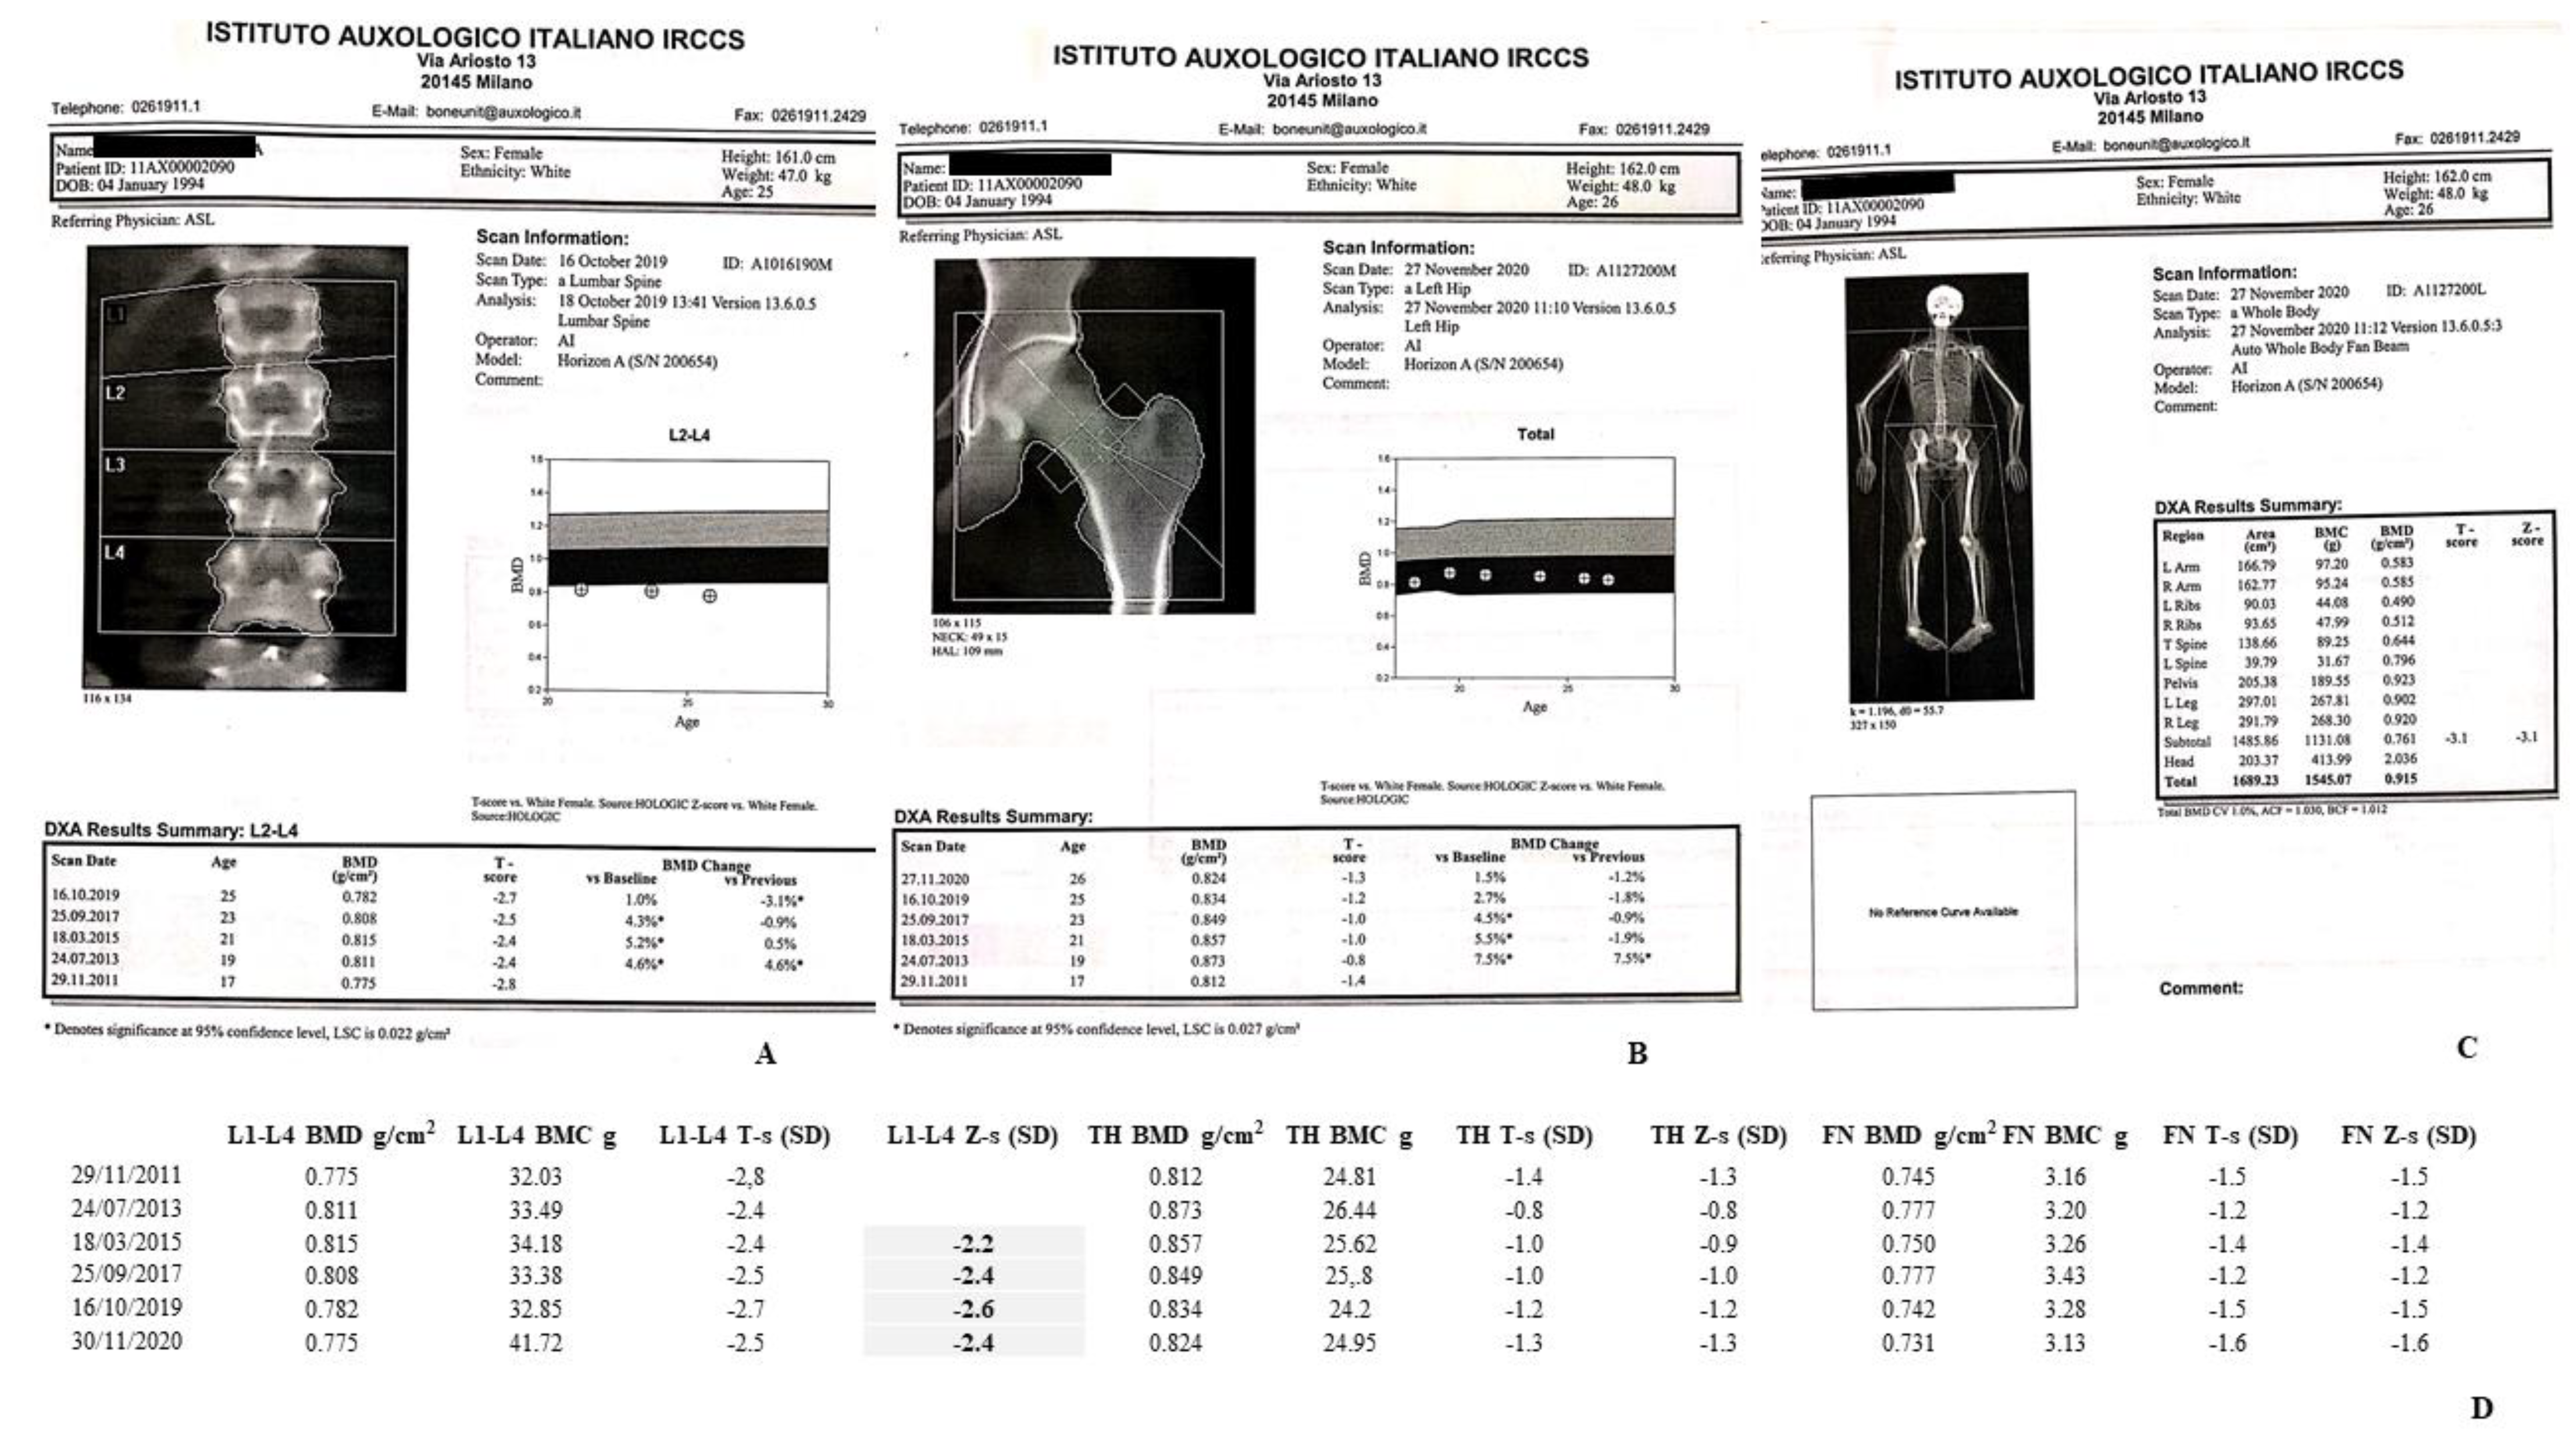

3.1. Bone Phenotyping

3.1.1. Dual Energy X-ray Absorptiometry (DXA)

4.1. DXA Scans

4.1.1. II-1 Tw1

4.1.2. II-2 Tw2